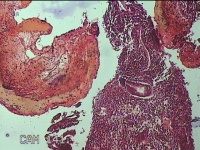

宫腔内容物

性别

女

年龄

36岁

临床诊断

异常子宫出血 附件囊肿改变

一般病史

阴道不规则流血17天。

标本名称

大体所见

灰白暗红色不规则碎组织1.8x1.3x0.3cm一堆。

图2

经期内膜+增殖期内膜。